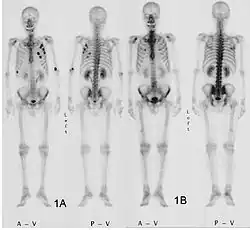

Scintigraphie corps entier avec 99mTc-HDP de la patiente avec une fracture du bras due à une métastase du cancer du sein

La scintigraphie osseuse est actuellement encore le meilleur moyen de diagnostic des métastases osseuses. Ce procédé est relativement sophistiqué, coûteux et soumis à quelques limites diagnostiques[90]. Contrairement à la radio, on peut avec la scintigraphie représenter assez simplement l'ensemble des attaques du squelette[87]. Une scintigraphie osseuse est normalement bien plus sensible pour la détection des métastases osseuses qu'une radio. La sensibilité de la scintigraphie osseuse est assez élevée, avec 95 %. En moyenne, avec cette méthode, les métastases osseuses sont détectées six mois avant leur mise en évidence sur la radio[113]. Par contre la spécificité est substantiellement plus faible[114], car presque toutes les modifications tumorales ou inflammatoires du squelette conduisent à un enrichissement en radiotraceurs dans le voisinage. Le remodelage plus élevé et les processus de réparation dans la bordure des métastases osseuses ostéolytiques conduisent à une accumulation plus élevée du radiotraceur, visible comme un « point chaud » sur l'image de scintigraphie[115]. Un phénomène observable de rebond (flare up) peut être dû à l’augmentation de l’activité ostéoblastique au niveau des zones d’ostéolyse tumorale clinique, dont la colonisation métastatique a été éradiquée par le traitement ; il ne doit pas être confondu avec une progression métastatique, au risque de modifier le traitement de façon intempestive[116]. Dans les métastases osseuses de cancer du poumon ou du sein, la néoformation réactive d'os peut dans de rares cas être absente[117]. Sur la scintigraphie, ceci apparaît alors comme un « point froid », un domaine avec une absorption réduite du radiotraceur[118].

Pour le myélome multiple purement ostéolytique, on ne reconnaît sur la scintigraphie osseuse aucun changement[87]. Alors que sur la radio, le résultat de la sommation de tous les processus d'échange de matière dans l'os se voient sur une longue période, la scintigrapie osseuse présente un instantané des processus d'échange de matière en cours dans l'os. C'est pourquoi les métastases osseuses ostéocondensantes, qui se déroulent avec un taux d'échange de matière très bas, restent imperceptibles à la scintigraphie[119].

La scintigraphie osseuse est avant tout utilisée pour le contrôle de la thérapie, que ce soit une chimiothérapie, une radiothérapie externe ou métabolique, pour la détermination des stades, notamment pour les cancers avec tumeur primitive inconnue, et pour le suivi après cancer[87].